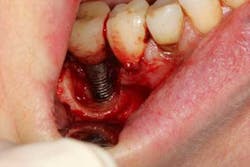

A 52-year-old woman with a noncontributory medical history, taking no medications with no reported food or drug allergies, was referred to my office from a general dentist in order to obtain a second opinion. She had a lower right premolar implant placed in an oral surgery office five years ago that was suffering from severe peri-implantitis. (Fig. 1) Her first dentist told her that the implant had to be removed and that her treatment options were a fixed partial denture in the form of a three-unit bridge or a partial denture because re-implantation was not feasible. In addition, he sent her to a periodontal office that verified his statement, telling the patient that because of nerve proximity and the poor chance of ridge augmentation, re-implantation was unlikely. When she asked if saving the implant was possible, both the dentist and the periodontist told the patient that because of the level of bone loss, regenerative treatment would not work.Fig. 4